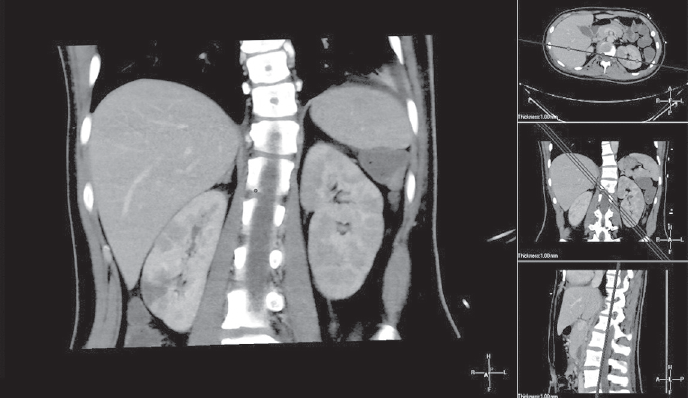

По данным компьютерной томографии от 31.12.14 — признаки выпотного плеврита с обеих сторон, более выраженного слева. Ателектазы в S9 с обеих сторон компрессионного характера. Лимфоаденопатия внутригрудных лимфатических узлов. Перикардит. Отмечается отек мягких тканей вокруг передних отделов ключицы с наличием мелких пузырьков газа. Выявленные изменения в головке левой ключицы соответствуют послеоперационным изменениям. Во всех третях правой почки прослеживаются множественные участки пониженного накопления неправильной треугольной формы, широким основанием прилежащие к капсуле почки, захватывающие кортикальный и медуллярный слои, наиболее вероятно являются проявлениями инфаркта правой почки. Отек паренхимы левой почки (рис. 1, 2).

Рис. 2. Компьютерная томограмма пациентки А., 16 лет. Инфаркт правой почки

Fig. 2. CT scan of 16-year old female patient A. Infarction of the right kidney